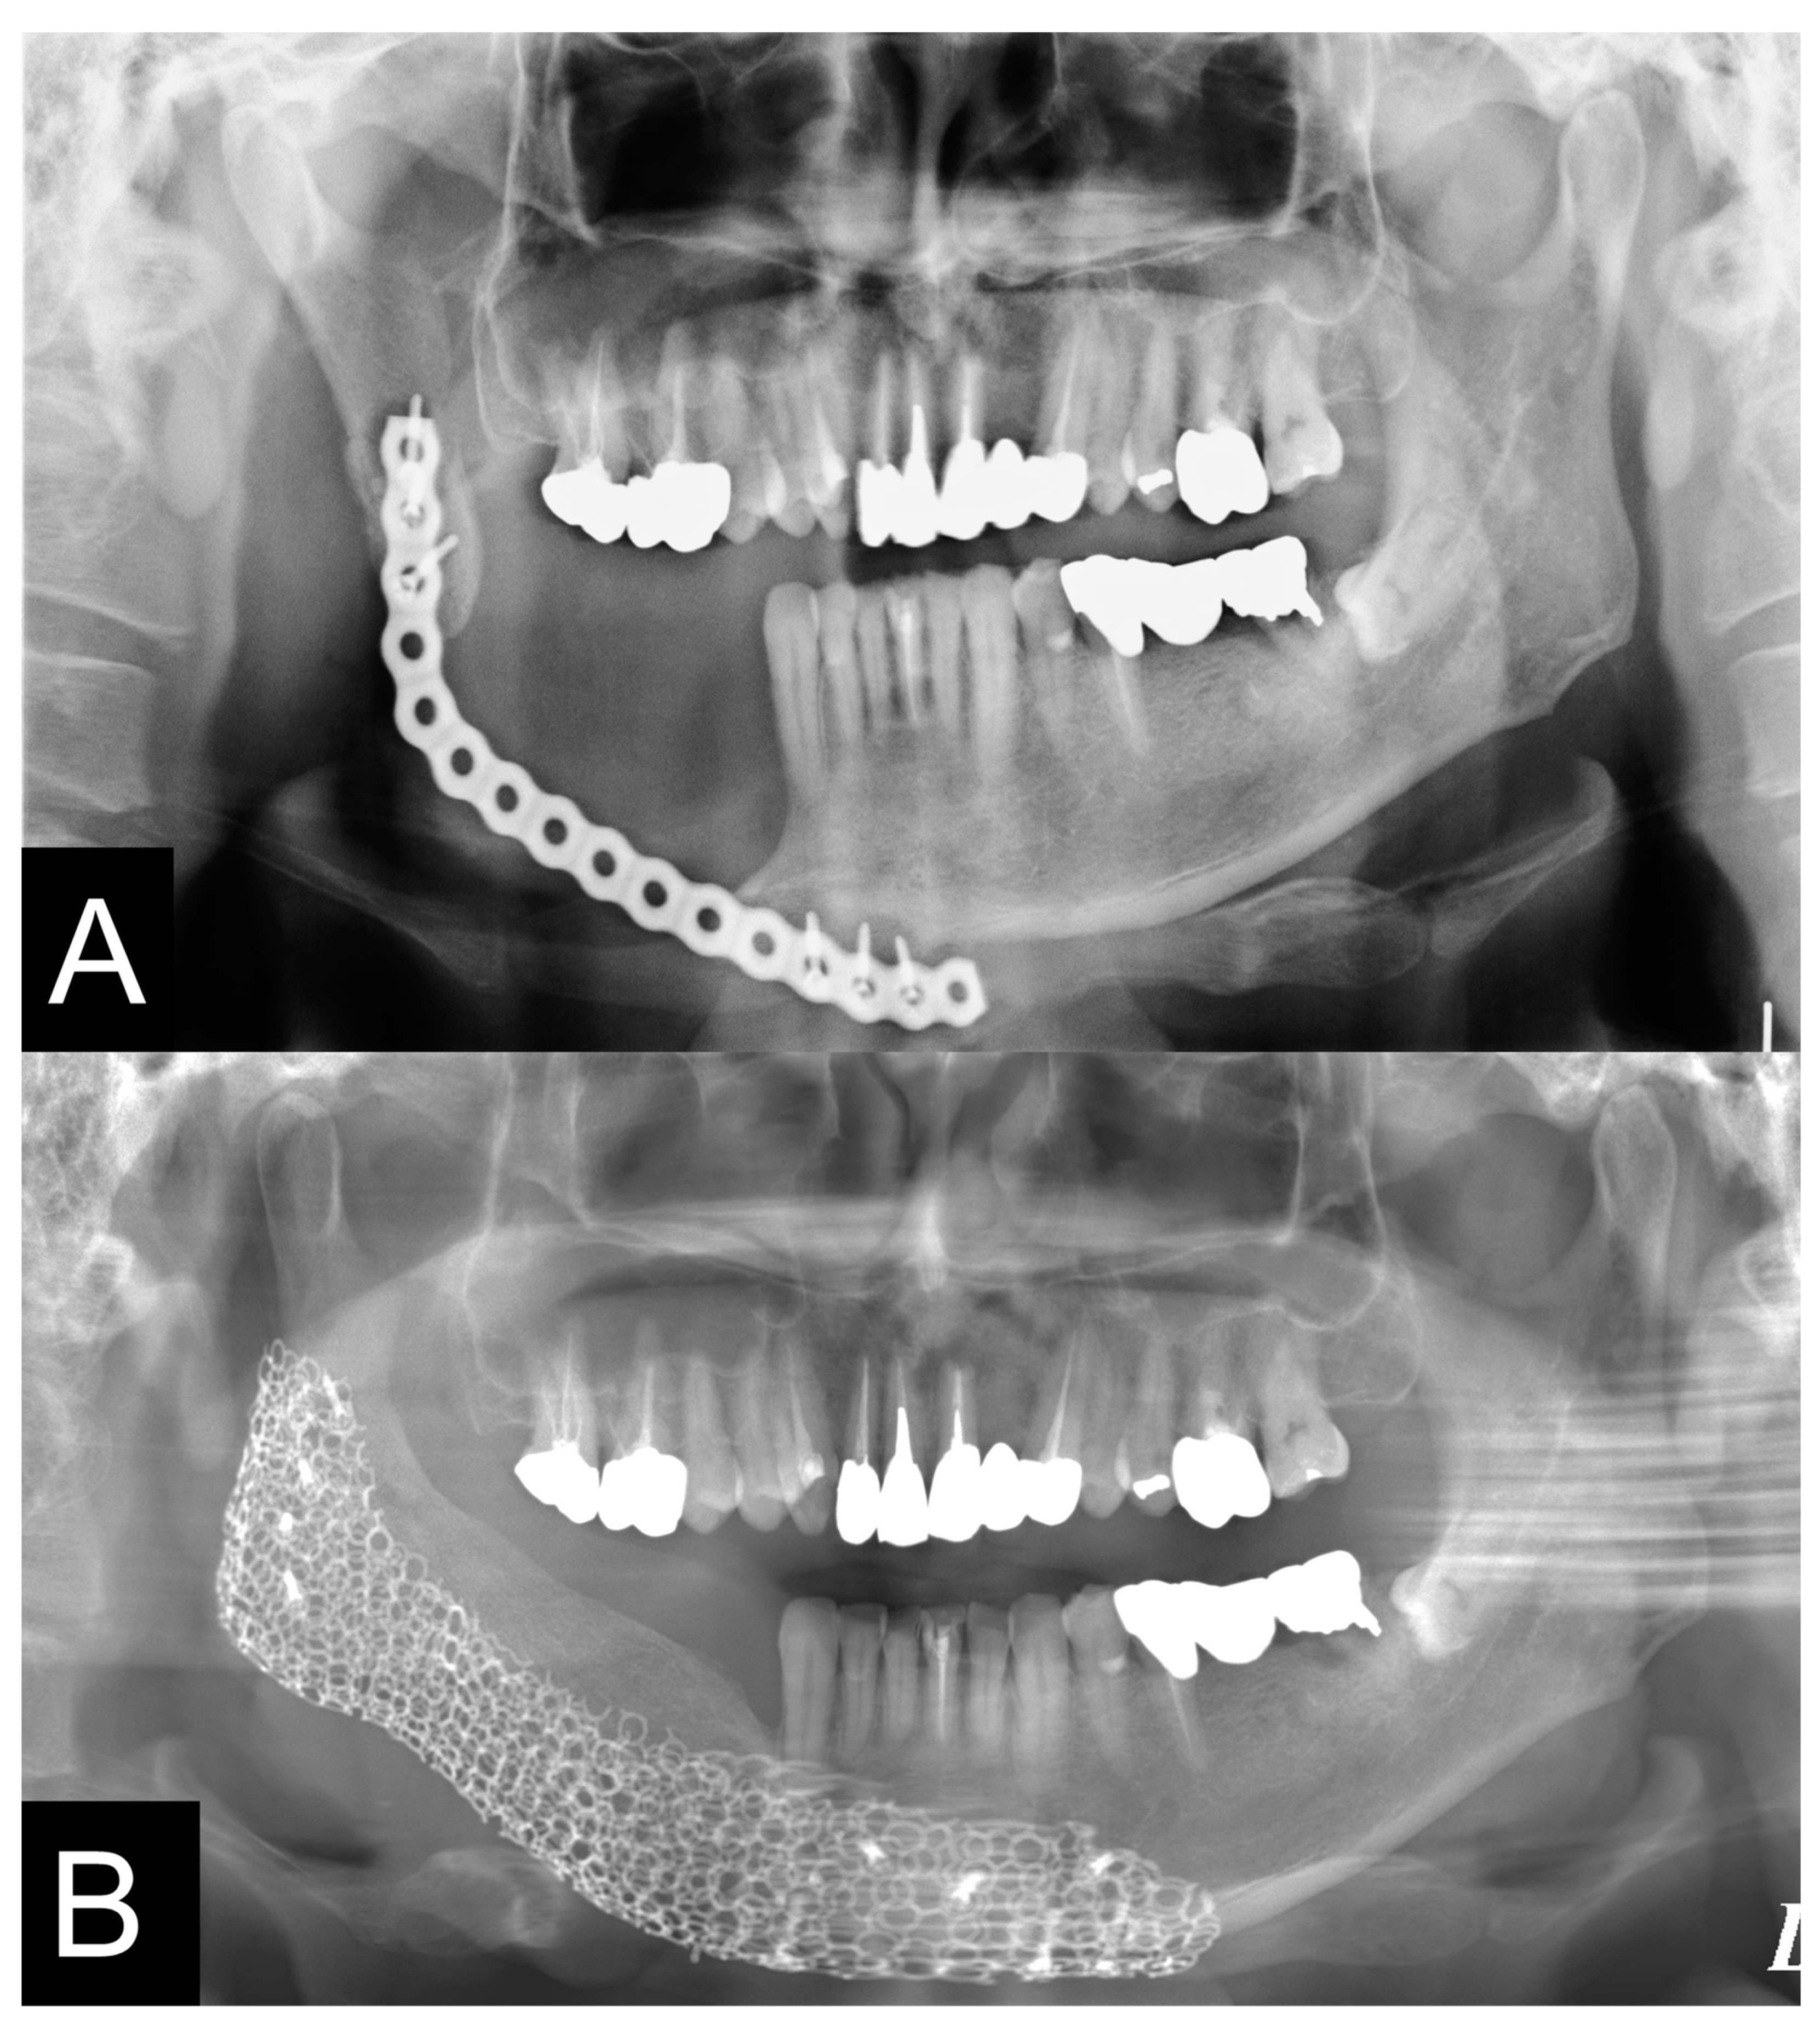

| Case | Gender | Age | Diagnosis of Primary Disease | Primary Reconstruction | Bone Defect | Classification Of Js Brown | Schematic of Mandibular Defect |

|---|---|---|---|---|---|---|---|

| 2 | M | 73 | SCC Gingiva | Surgical plate | Segmental bone defects | Body-chin Class II | ![]() |

| 3 | F | 78 | SCC Floor of mouth | Rectus abdominis musculocutaneous flap and surgical plate | Segmental bone defects | Body-chin Class III | ![]() |

| 5 | F | 69 | SCC Gingiva | Surgical plate | Segmental bone defects | Ramus-body Class I | ![]() |

| 9 | M | 58 | Mucoepidermoid carcinoma Floor of mouth | Vascularized fibular bone graft | Segmental bone defects | Ramus-body-chin Class III | ![]() |

| 10 | M | 60 | Ameloblastoma | Fractured surgical plate | Segmental bone defects | Ramus-body Class I | ![]() |

| 11 | F | 62 | SCC Gingiva | Fractured surgical plate | Segmental bone defects | Ramus-body Class II | ![]() |

| 13 | F | 50 | Odontogenic myxoma | Surgical plate | Segmental bone defects | Body-chin Class II | ![]() |

| 14 | M | 74 | SCC Gingiva | Surgical plate | Segmental bone defects | Body-chin Class III | ![]() |

| 15 | M | 62 | SCC Gingiva | Vascularized scapular bone graft (non-union) | Segmental bone defects | Body-chin Class I | ![]() |

| 16 | F | 45 | Ameloblastoma | Surgical plate | Segmental bone defects | Ramus-body Class I | ![]() |

| 18 | M | 63 | Ameloblastoma | Fractured surgical plate | Segmental bone defects | Ramus-body-chin Class III | ![]() |

| Case | Virtual Reconstruction Technique | Preoperative Simulation of PCBM Amount | The Reality of PCBM Quantity | Preoperative Length (mm) | Postoperative Length (mm) | A Preoperative Sum of the Condylar Axial Angles (Degree) | A Postoperative Sum of the Condylar Axial Angles (Degree) |

| 2 | Level 2 | 11.3 cc | 20 cc | 45.4 mm | 50.4 mm | 141° | 151° |

| 3 | Level 2 | 11.9 cc | 23 cc | 36.0 mm | 36.0 mm | 150° | 151° |

| 5 | Level 2 | 11.3 cc | 17 cc | 46.0 mm | 53.5 mm | 153° | 142° |

| 9 | Level 2 | 20 cc | 40 cc | 63.4 mm | 65.7 mm | 106° | 132° |

| 10 | Level 2 | 19.3 cc | 40 cc | 70.7 mm | 77.7 mm | 129° | 136° |

| 11 | Level 2 | 10 cc | 15 cc | 56.3 mm | 53.1 mm | 136° | 140° |

| 13 | Level 2 | 10 cc | 19 cc | 35.3 mm | 42.4 mm | 150° | 145° |

| 14 | Level 3 | 10.4 cc | 20 cc | 56.3 mm | 59.6 mm | 172° | 161° |

| 15 | Level 3 | 10.6 cc | 24 cc | 54.5 mm | 61.0 mm | 197° | 197° |

| 16 | Level 2 | 9.6 cc | 21 cc | 30.8 mm | 36.0 mm | 164° | 160° |

| 18 | Level 2 | 17.7 cc | 32 cc | 54.5 mm | 72.5 mm | 137° | 140° |